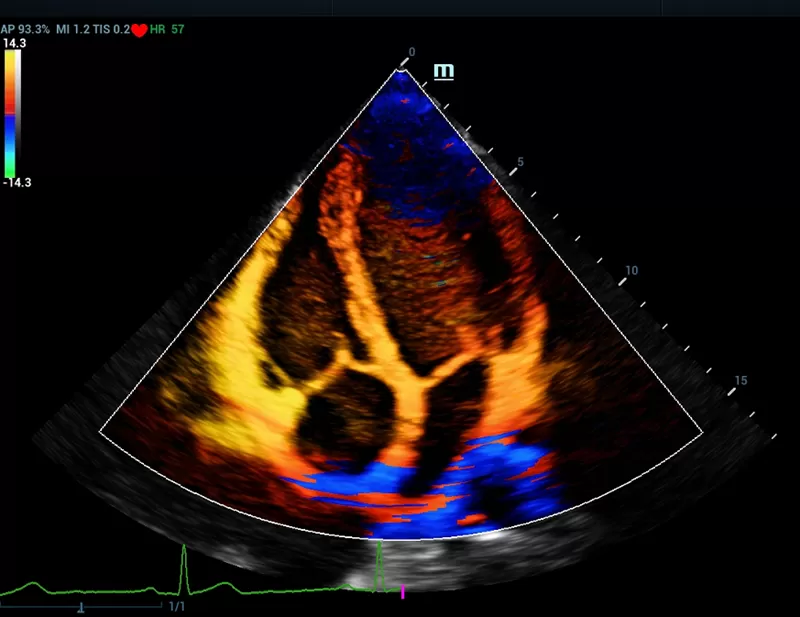

The Resona series, stands out not only for its cutting edge imaging technology but also for its flexible analysis tools offering high display quality and increased diagnostic precision.

- Dynamic Focusing

- HD Scope